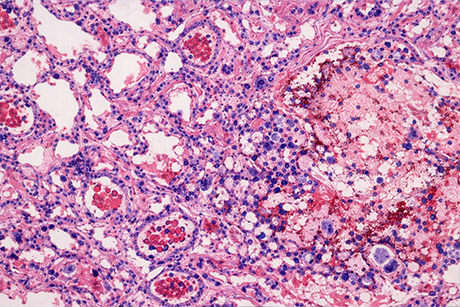

Biopsja to pobranie tkanki lub komórek do badania patomorfologicznego. Podczas bronchoskopii możemy również wykonać biopsję – pobrać wycinki ze zmian wewnątrzoskrzelowych. Odmianą bronchoskopii jest tzw. EBUS (ultrasonografia przedoskrzelowa), czyli badanie wykonane bronchoskopem wyposażonym w głowicę ultrasonograficzną, co pozwala dokładnie ocenić patologiczne zmiany leżące pozaoskrzelowo. Pod kontrolą EBUS można wykonać biopsję

Ocena patomorfologiczna

Ocena patomorfologiczna to kluczowy moment całej diagnostyki. Pobrany materiał biologiczny, tkankowy czy komórkowy, jest dowodem potwierdzającym lub wykluczającym chorobę. Wynik badania patomorfologicznego zamyka diagnostykę wstępną.